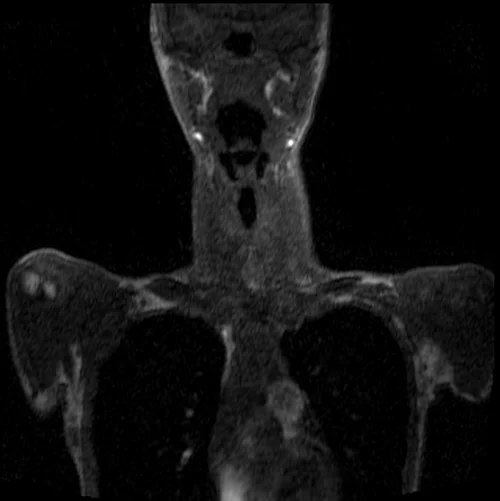

MRA subclavian artery coronal T1 3D FLASH images